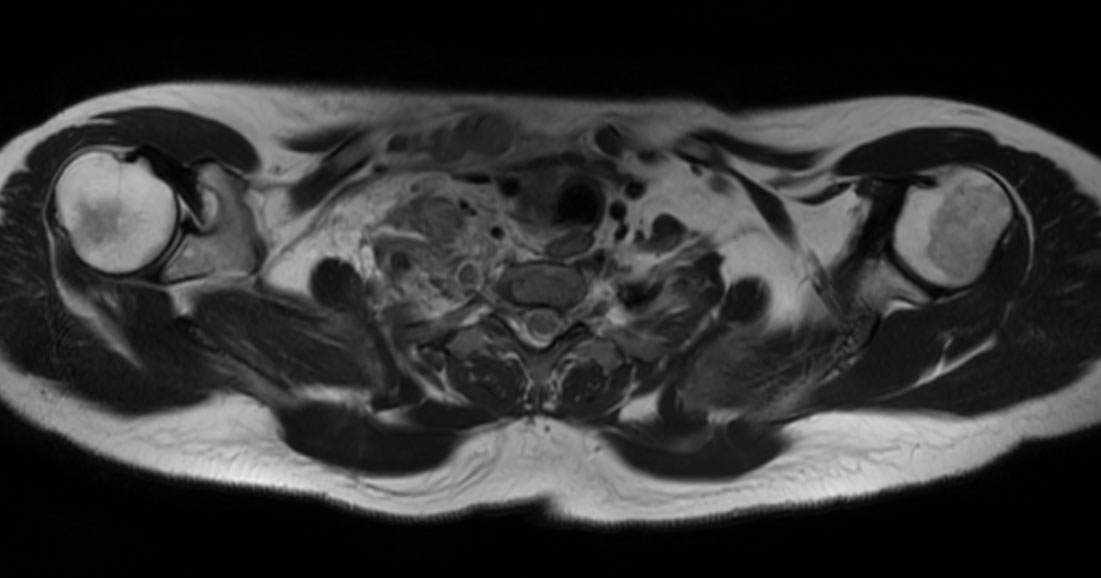

Axial T2w mDIXON XD TSE (Water only)